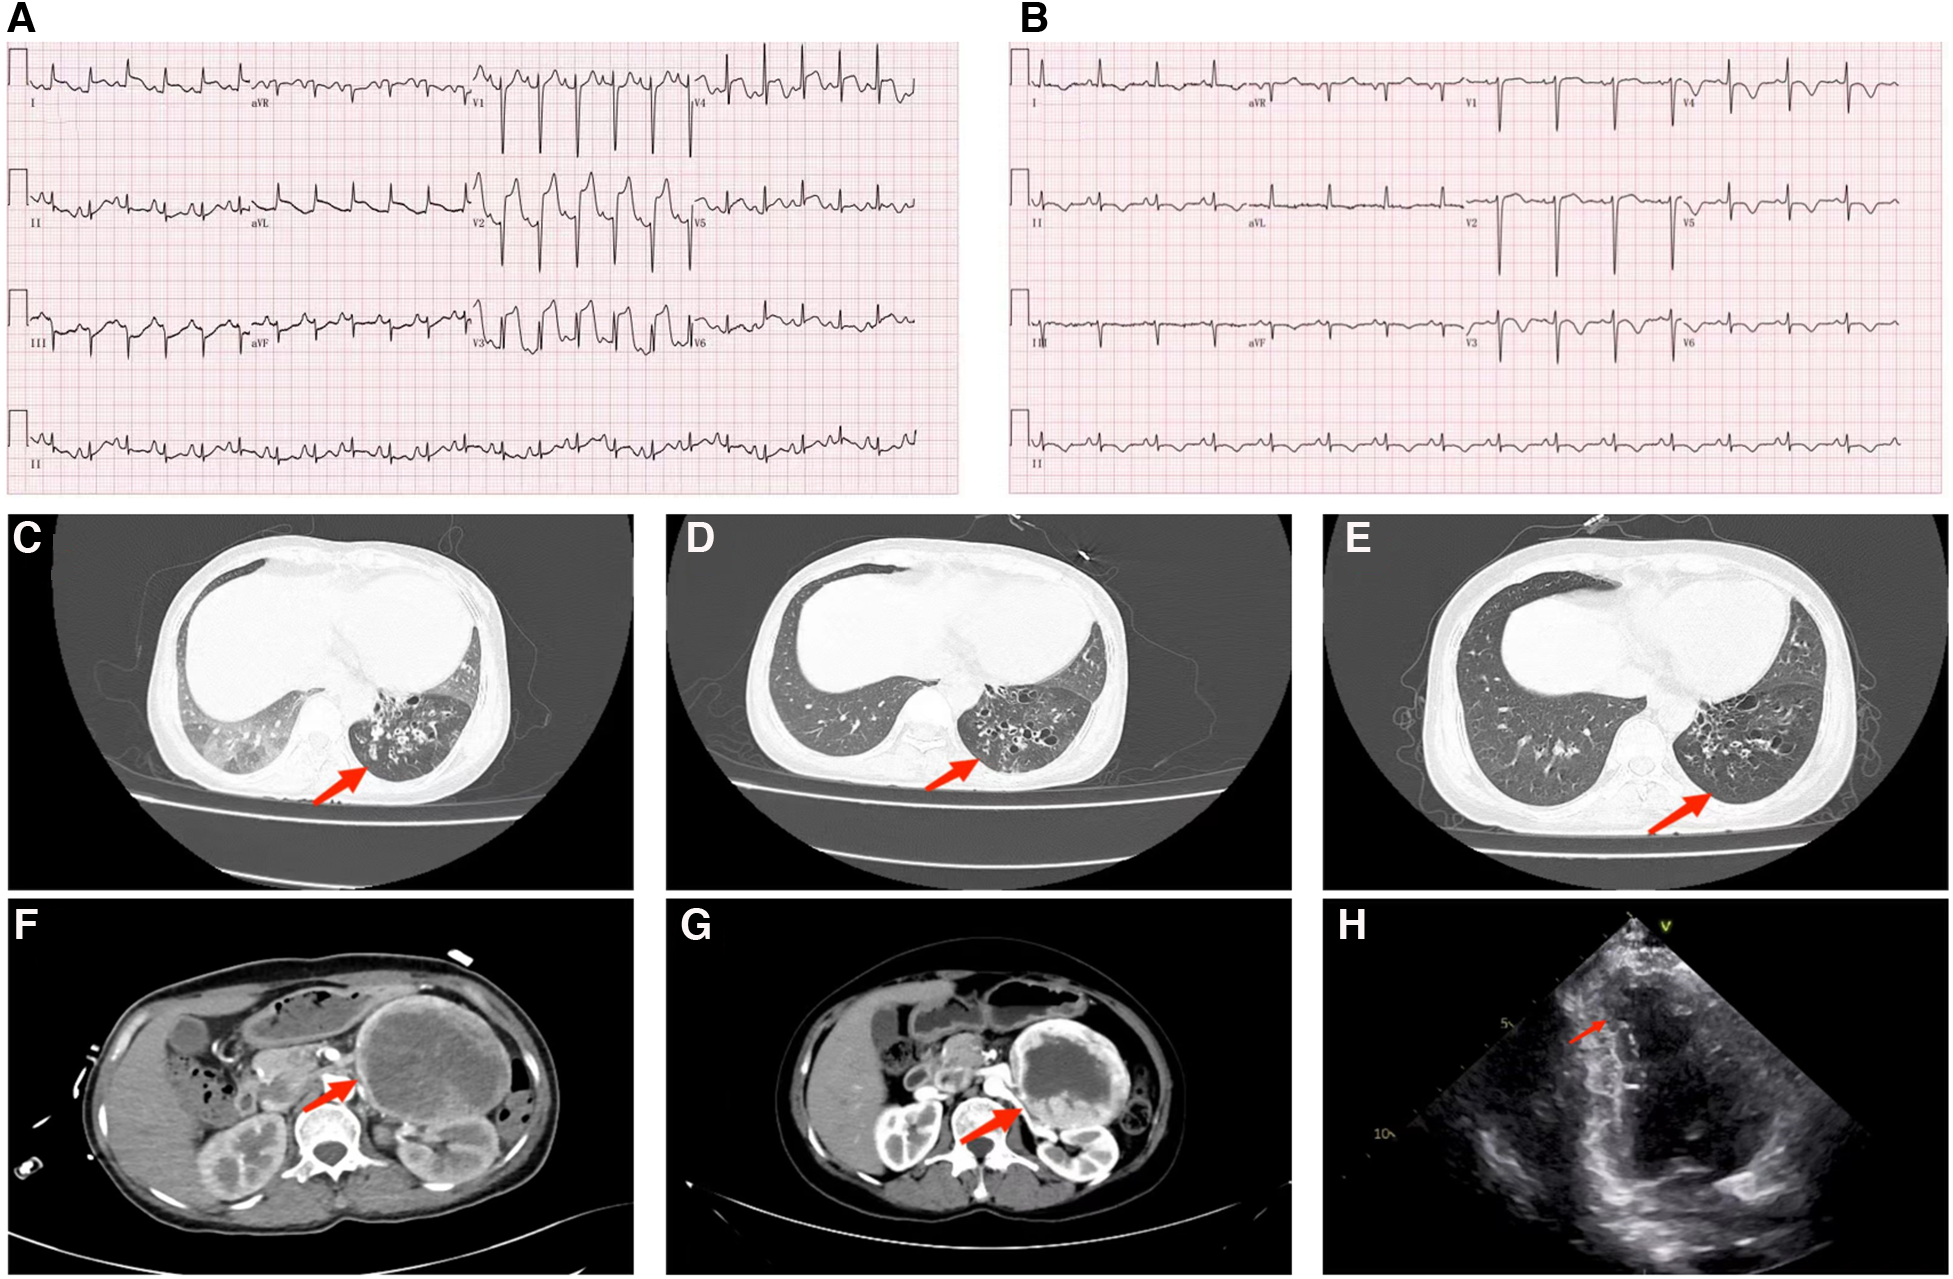

The initial laboratory data is given in Table 1. Furthermore, the peak level of cardiac troponin I (cTnI) was 27.3 ng/ml. On admission, the ECG (Figure 1) showed elevated ST segments in lead V1–V6. Ultrasonic cardiography (UCG) suggested that the left ventricular end-diastolic (LVED) diameter was 50 mm, ejection fraction (EF) was 52%, and the thickness of the interventricular septum, the middle and lower segment of the interventricular septum, the pulsatile amplitude of the left ventricular (LV) apex and the inferior wall of the LV anterior wall was weakened. The LV apex was slightly dilated outward. Lung computerized tomography (CT) revealed trachea and sputum retention, left lower lung bronchiectasis with infection and bilateral lung inflammation (Figure 1). We considered some inflammatory manifestations of lung CT, which represented pulmonary congestion from acute heart failure.

FIGURE 1

Figure 1. (A) ECG of the admitted patient; (B) ECG of patients after treatment with phenoxybenzamine. (C) Lung CT examination at admission shows that bronchiectasis of the lower lobe of the left lung is associated with infection, bilateral lung inflammation (red arrow). (D) Pulmonary CT on the second day after the addition of phenbenamine, displays Bronchiectasis of the lower lobe of the left lung with slight relief of infection (red arrow). (E) Preoperative lung CT re-examination depicts that the degree of bronchiectasis with infection in the lower lobe of the left lung is slightly less than that of the previous one (red arrow). (F) Abdominal enhanced CT manifests that mass high density mixed density shadow can be observed in the left middle and upper abdomen; the maximum level is about 7.7 cm × 9.4 cm (red arrow). (G) Preoperative abdominal CT review, appearing roughly similar to the previous image (red arrow). (H) Systolic period in the apical two chamber (A2C) view: displays the apical wall of left ventricle becomes thinner; outward bulg and reduction of amplitude of motion (red arrow).

The patient was admitted with more than 24 h ST-segment elevation myocardial infarction (STEMI) and pulmonary infection. Considering her stable hemodynamics, absence of chest pain and the strong rejection from his family, we did not immediately perform a coronary angiography on the patient. Furthermore, the patient was given a series of routine treatments, including aspirin (100 mg, QD), clopidogrel (75 mg, QD), enoxaparin sodium (40 mg, Q12 h), metoprolol succinate (23.75 mg, QD), torasemide (20 mg, QD), acetylcysteine (0.6 g, BID), non-invasive ventilator-assisted ventilation and diuresis. Because of concern for infection the patient was treated with piperacillin-tazobactam. The second day following admission, the patient had a fever of 37.6°C, aggravated nausea and vomiting, sudden palpitation, sweating, and a flushing complexion. ECG showed a heart rate of 130 bpm, blood pressure of 207/110 mmHg, and frequent paroxysmal ventricular tachycardia. UCG indicated left atrial enlargement (40 mm × 46 mm × 50 mm), LV enlargement (52 mm), EF: 44%, interventricular septal thickening (12 mm), abnormal LV movement, neck narrowing during LV contraction and balloon-like dilation of the apex of the heart. we immediately improved the coronary artery computed tomography angiography (CTA) examination. The results suggested unobstructed coronary artery flow with no obvious stenosis. Therefore, coronary obstruction as the cause of the AMI was excluded, and TCM was diagnosed based on international takotsubo diagnostic criteria (2). Moreover, low molecular weight heparin and antiplatelet therapy were discontinued. Warfarin was given to prevent apical thrombosis. Since pheochromocytoma could not be ruled out, we replaced metoprolol succinate with amiodarone to control the patient's heart rate and switched from piperacillin-tazobactam to meropenem. Abdominal color ultrasound, plasma catecholamine and its metabolites were detected. Abdominal color ultrasound exposed a heterogeneous echo mass of 94 mm × 90 mm under the left kidney. In addition, an enhanced abdominal CT scan (Figure 1) confirmed the presence of a space-occupying lesion in the posterior peritoneal region of the left mid-epigastric region, which was a neurogenic tumor. In recumbent position, plasma levels of various catecholamines and their metabolites rose significantly, including methoxytyramine 126.9 pg/ml (reference range < 18.4 pg/ml), dopamine 320.6 pg/ml (reference range < 30 pg/ml), norepinephrine 12,377.6 pg/ml (reference range: < 750.0 pg/ml), epinephrine 601.6 pg/ml (reference range: < 111.0 pg/ml), normetanephrine 23,774.9 pg/ml (reference range < 165.0 pg/ml), and metanephrines 12,37.0 pg/ml (reference range < 98.5 pg/ml). The patient was clinically diagnosed with pheochromocytoma and was prescribed phenoxybenzamine (10 mg, QD) and metoprolol succinate (95 mg, QD). To rule out familial pheochromocytoma, the patient's immediate family members were also examined for Plasma fractionated metanephrines and questioned about the relevant clinical manifestations; however, no abnormalities were found.

After adjusting the treatment protocol, the liver and kidney function of the patient and the elevated ST segment of the ECG returned to normal (Figure 1). However, body temperature, blood pressure, and heart rate remained inadequately regulated. To devise an appropriate treatment plan, a whole-hospital discussion was carried out. The Phenoxybenzamine was adjusted to 20 mg three times a day for one month, after which the resection of pheochromocytoma would be evaluated. The primary liver and kidney diseases was excluded. Due to a series of negative pathogenic tests, we suggested further examination of bronchoalveolar lavage fluid to determine the infection's cause. However, the patient's family refused. After 24 h of intensive Phenoxybenzamine therapy, the symptoms of palpitation, sweating, and flushed face were significantly alleviated. Moreover, body temperature, blood pressure and heart rate gradually returned to normal. The lung re-CT examination displayed bilateral lungs had less inflammation than previously (Figure 1); thus, we downgraded meropenem to piperacillin-tazobactam sodium. At the same time, metoprolol succinate was adjusted to 47.5 mg twice a day. As the condition gradually improved, the patient was then discharged from the hospital and instructed to continue oral maintenance treatment with Phenoxybenzamine (20 mg, TID) and metoprolol succinate (47.5 mg, BID). The important laboratory and physical alterations throughout the entire treatment process are detailed in Figure 2.

After one month, the patient's condition stabilized, and a preoperative evaluation was conducted in our hospital. UCG showed that the LVED was 51 mm, EF was 57%, the thickness of the ventricular septum was 10 mm, and decreased pulsatile amplitude of the basal segment of the LV inferior wall. Other examinations also met surgical requirements (Figure 1). Adrenal pheochromocytoma was confirmed by resection and pathological examination (Figure 3, Pathology). In the outpatient clinic, the UCG were normal one week after the operation.